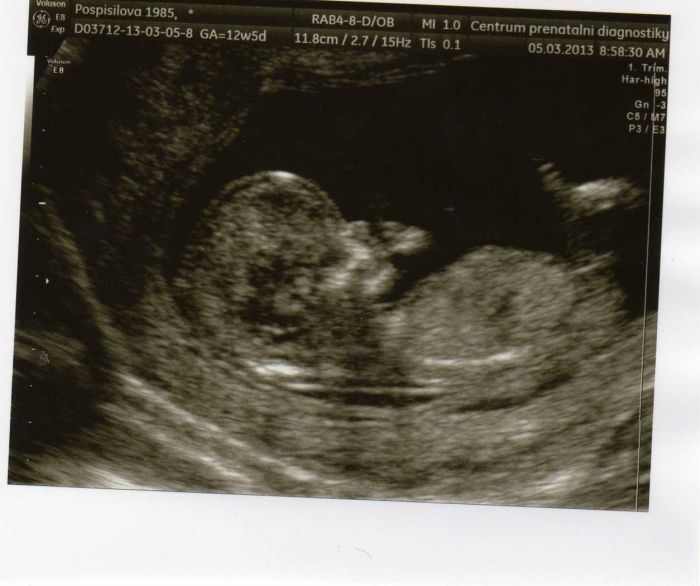

Tak mi kočárek kupovat nebudeme,mi máme po dceři sice je červený a ted to má být kluk ale to neřeším

a sporták máme zelený takže pohoda.Také vám představuji našeho prdolku. Nemůžu se dočkat až ucitím pohyby to prcka tay někdy mívám takové pocity že co když není něco v pořádku když o něm měsíc nic nevím a ani ho necítím,potom už to bude zase o něčem jiném.Když se delší dobu nepohne tak do něj trošku drcnu a hned vím že je vše ok jak se začne mrvit.Moje dcera když byla v břísku tak měla strašně často šťukavku dokonce nás doktor posílal i na speciální vyšetření zda je to nromální a prej jo aspon se o ni věděla že ji tam mám jak s mě třepalo pořád břicho